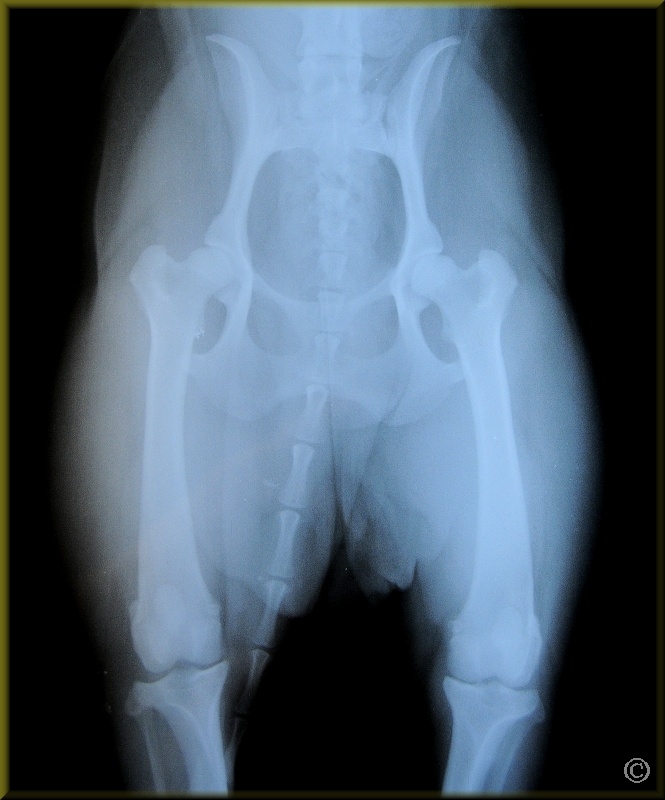

Ch. DarkStar Pua Manu - Birdie